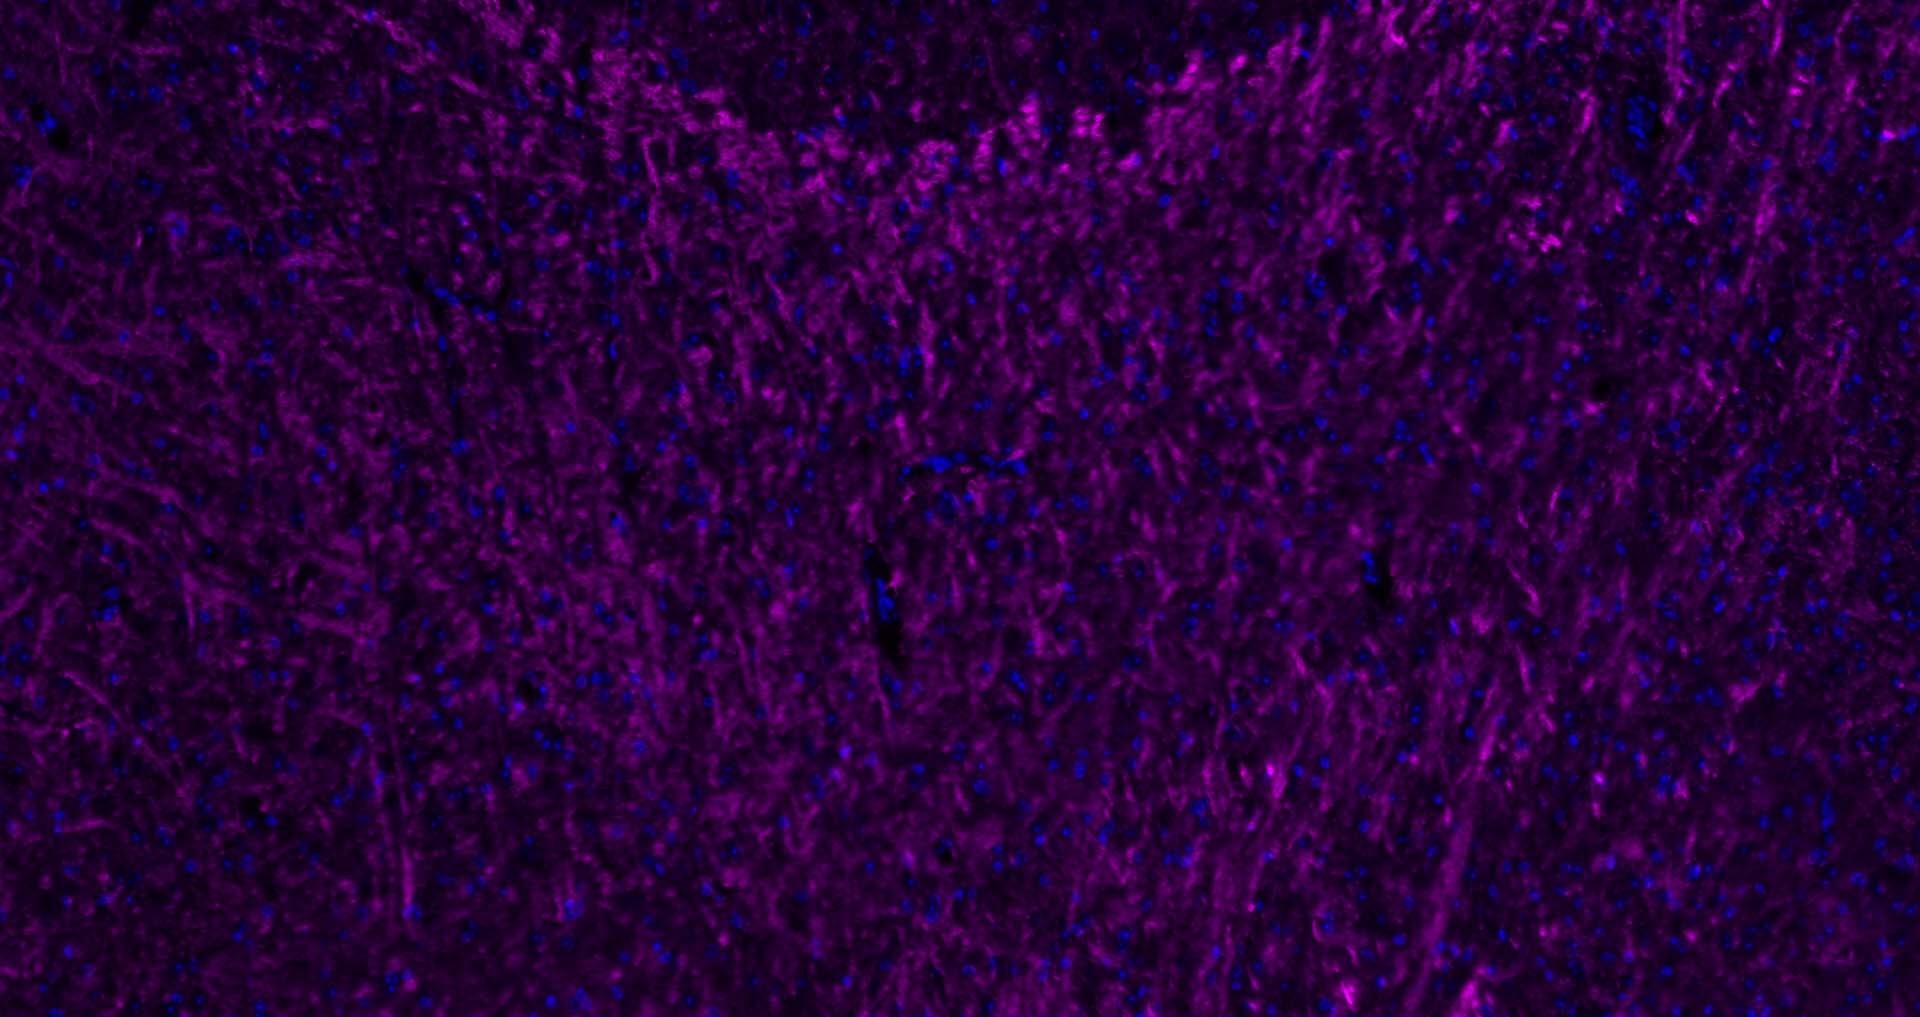

6. Paraformaldehyde-fixed, paraffin embedded Rat Cerebellum; Antigen retrieval by boiling in sodium citrate buffer (pH6.0) for 15 min; Antibody incubation with MBP Polyclonal Antibody, Unconjugated (TMAB-01110) at 1:200 overnight at 4°C. Followed by conjugated Goat Anti-Rabbit IgG antibody (Purple), DAPI (blue) was used to stain the cell nucleus.

7. Paraformaldehyde-fixed, paraffin embedded Human Cerebellum; Antigen retrieval by boiling in sodium citrate buffer (pH6.0) for 15 min; Antibody incubation with MBP Polyclonal Antibody, Unconjugated (TMAB-01110) at 1:200 overnight at 4°C. Followed by conjugated Goat Anti-Rabbit IgG antibody (Purple), DAPI (blue) was used to stain the cell nucleus.

8. Paraformaldehyde-fixed, paraffin embedded Human Left Parietal Lobe; Antigen retrieval by boiling in sodium citrate buffer (pH6.0) for 15 min; Antibody incubation with MBP Polyclonal Antibody, Unconjugated (TMAB-01110) at 1:200 overnight at 4°C. Followed by conjugated Goat Anti-Rabbit IgG antibody (Purple), DAPI (blue) was used to stain the cell nucleus.

9. Paraformaldehyde-fixed, paraffin embedded Mouse Cerebrum; Antigen retrieval by boiling in sodium citrate buffer (pH6.0) for 15 min; Antibody incubation with MBP Polyclonal Antibody, Unconjugated (TMAB-01110) at 1:200 overnight at 4°C. Followed by conjugated Goat Anti-Rabbit IgG antibody (Purple), DAPI (blue) was used to stain the cell nucleus.

10. Paraformaldehyde-fixed, paraffin embedded Mouse Cerebellum; Antigen retrieval by boiling in sodium citrate buffer (pH6.0) for 15 min; Antibody incubation with MBP Polyclonal Antibody, Unconjugated (TMAB-01110) at 1:200 overnight at 4°C. Followed by conjugated Goat Anti-Rabbit IgG antibody (Purple), DAPI (blue) was used to stain the cell nucleus.